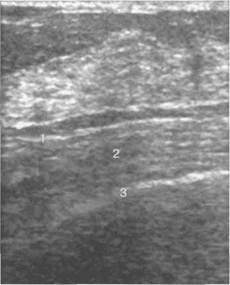

Рис. 10.27. Ультразвуковое изображение ретро­маммарного пространства у пациентки 47 лет.

1 — ретромаммарная жировая клетчатка; 2 — фасция грудной мышцы; 3 — задний листок рас­щепленной фасции. Между грудной мышцей и паренхимой железы лоцируется гипоэхогенный пласт ретромаммарной жировой ткани.